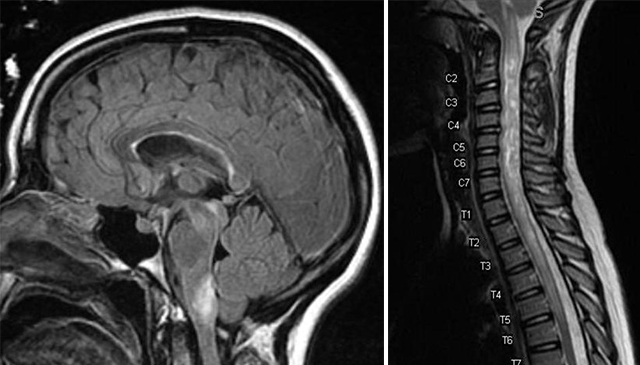

Transverse myelitis is a rare spinal cord disease that can cause varying degrees of disability. This condition causes inflammation that damages the spinal cord, disrupting pathways that relay information between the brain and the body. Individuals with transverse myelitis can experience a variety of symptoms that can include weakness, sensory alterations, and dysfunction of their autonomic nervous system, the system responsible for regulating breathing, digestion, reflexes, and more involuntary bodily functions. Although the cause of transverse myelitis is not always known, it can indicate a serious underlying disorder that might include multiple sclerosis, a rare neuro autoimmune disease, or serious infection. At UConn Health, we collaborate with experts to successfully treat and manage the immediate and long-term effects of transverse myelitis.